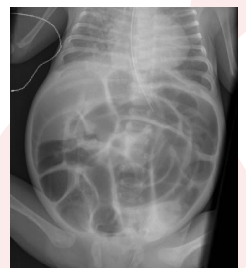

What is a Diaphragmatic Hernia

○Abd contents - organs in stomach push on chest cavity. protrude into lung cavity through diaphragm. The diaphragm didnt form completely , Life threatnening

Symptomsxx x.

○Resp distress, sunken abd, bowel sounds in chest

○Barrel chest bc everything being pushed up, dyspnea, cyanosis

○Diagnosis- US prior to birth or x ray after

○Medical Management: Life Threatening- Airway, NG/OGT, IVF, surgery